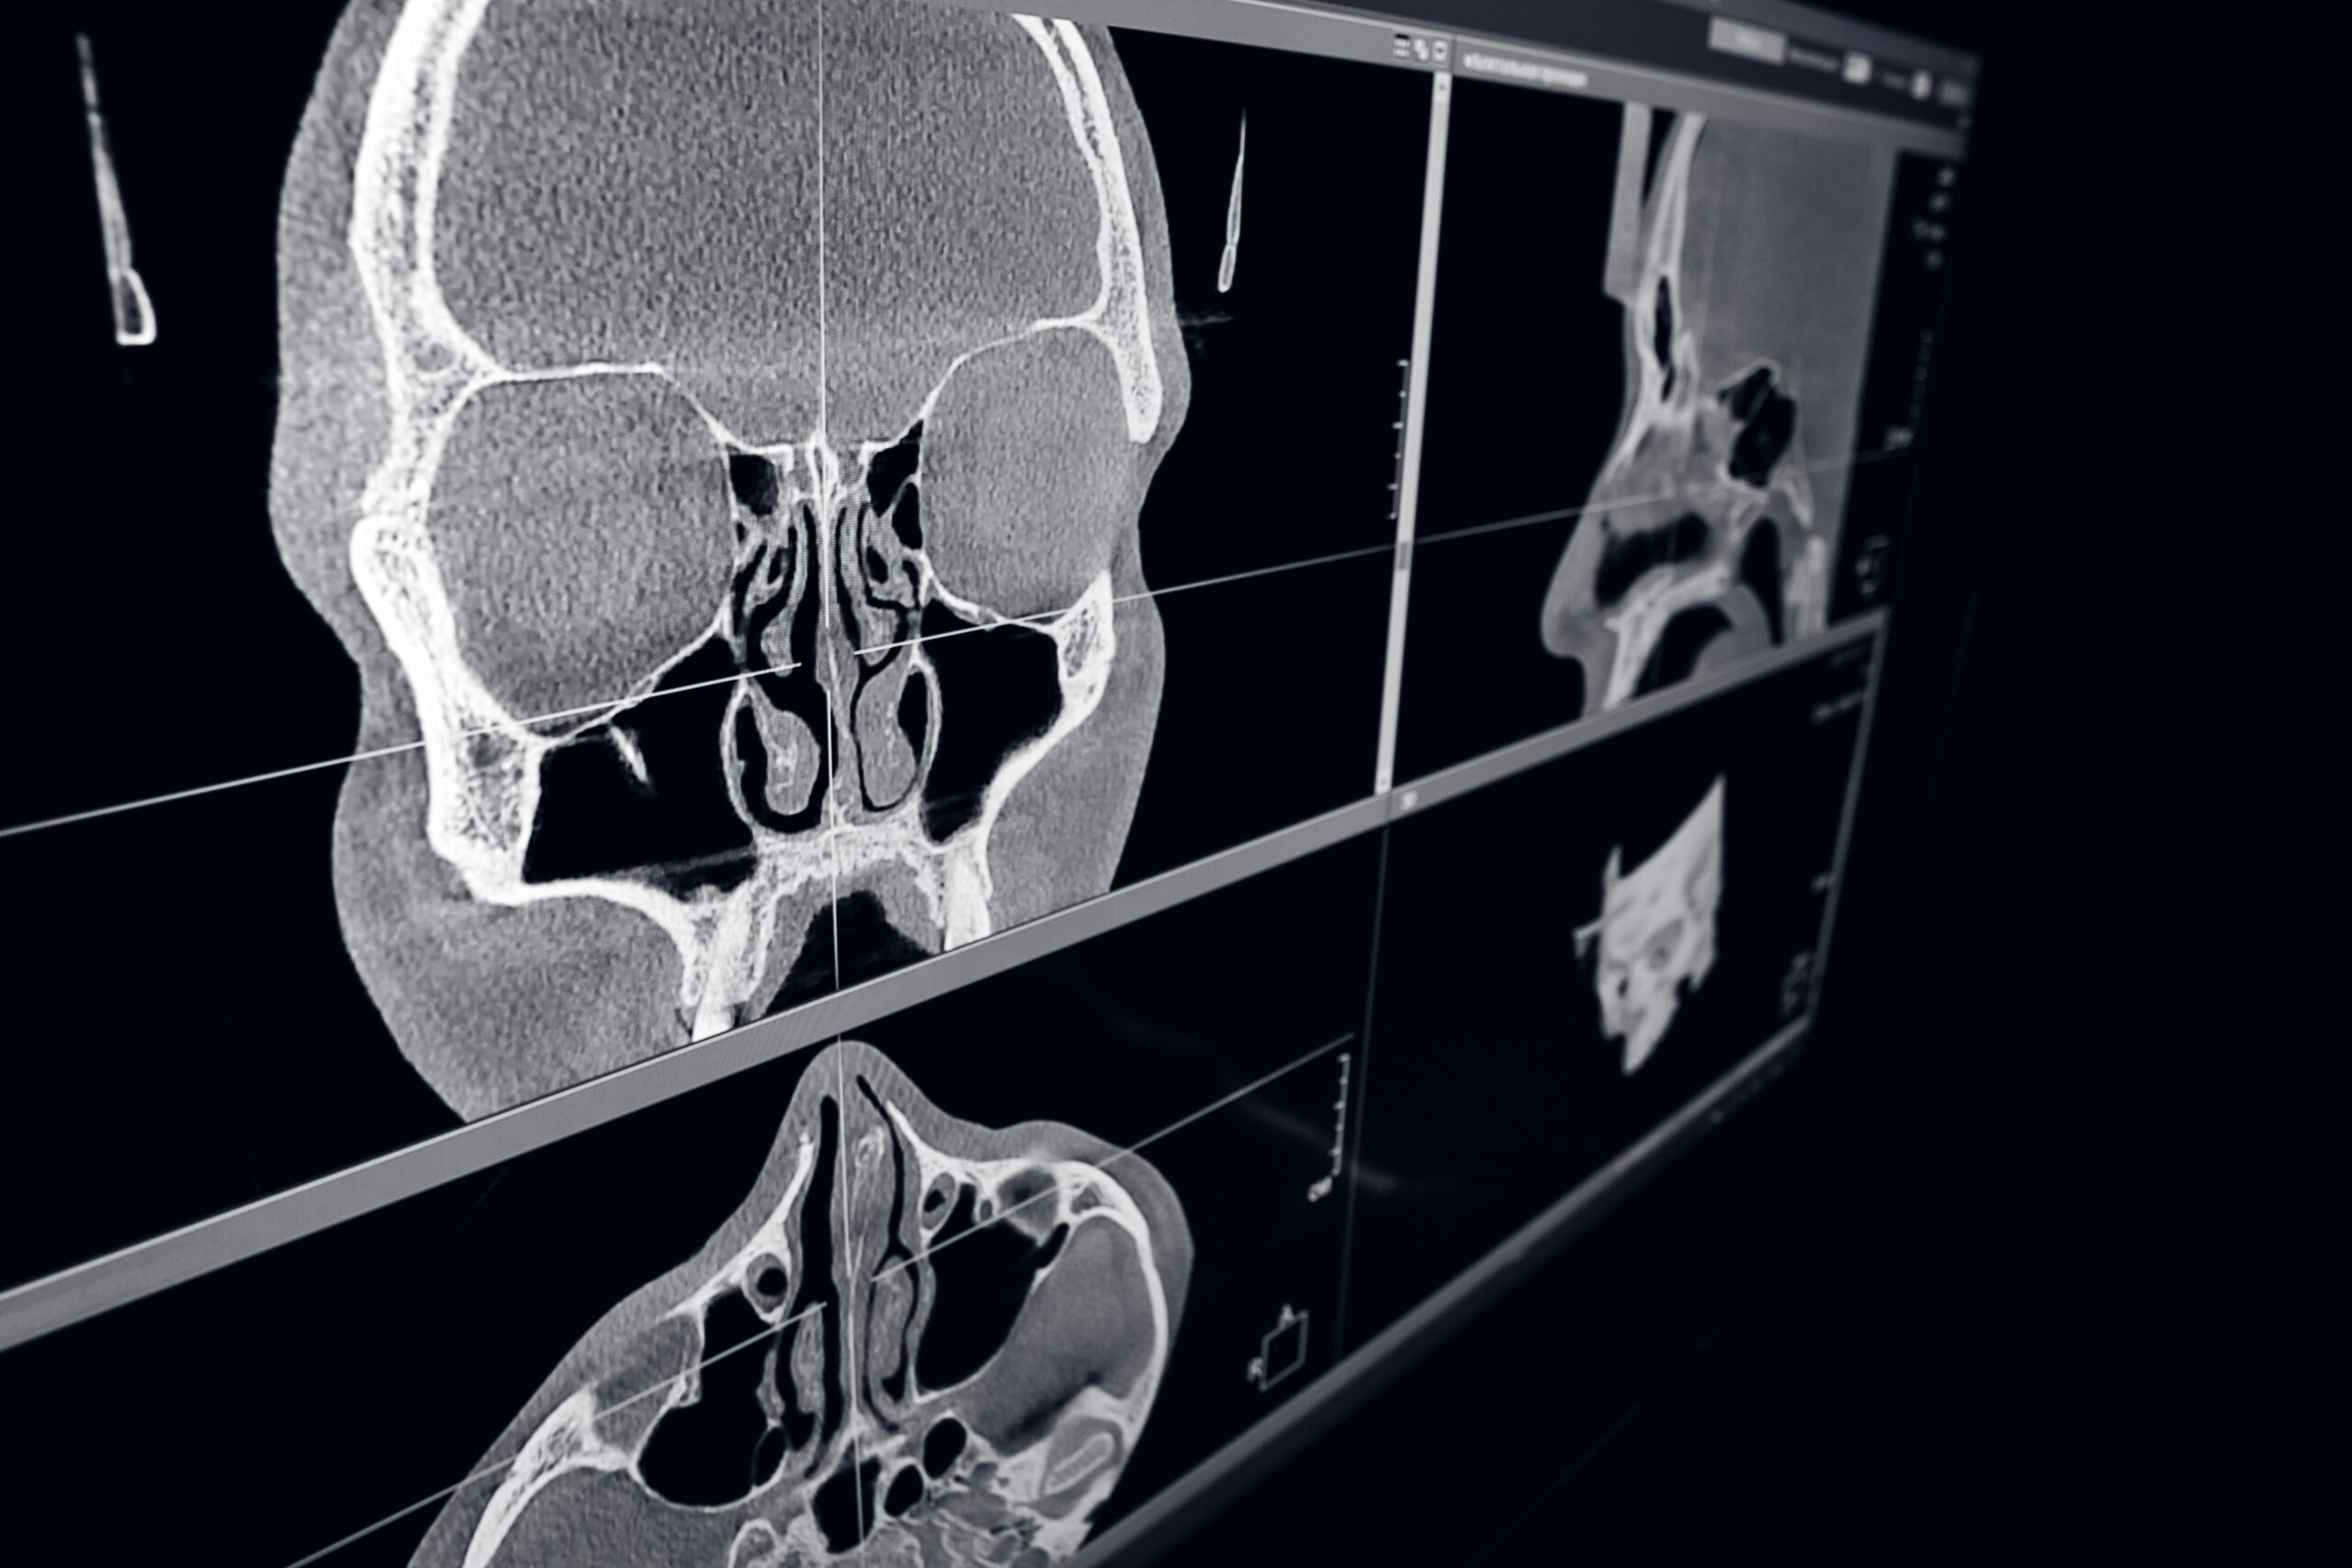

Компьютерная томография ЛОР-органов позволяет врачу в мелких деталях изучить состояние тканей пациента. Современное европейское оборудование создаёт чёткие и наглядные 3D изображения, которые значительно облегчают процесс диагностики.

Основная цель процедуры - определение особенностей анатомического строения носа и пазух пациента для оперативного выявления патологий или травм, даже на ранних стадиях развития.

Например, КТ позволяет определить наличие синусита в тех случаях, когда рентген не может предоставить достаточно чёткую информацию. Томограф помогает выявить образования, такие как полипы и кисты, в околоносовых пазухах. С его помощью специалисты могут контролировать динамику их развития.

• Врач получает 3D снимок, на котором в мельчайших деталях представлено строение носа и пазух пациента.